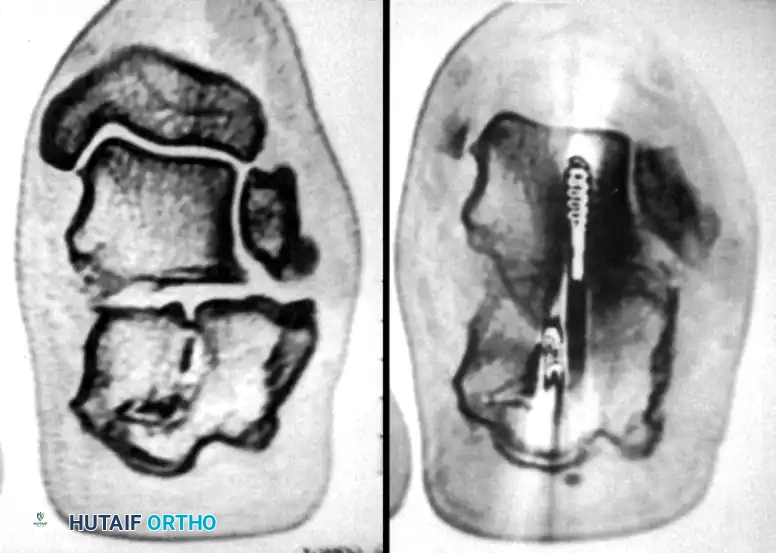

Meticulous preoperative planning is essential for successful percutaneous fixation. Standard radiographs, including lateral, axial (Harris), and anteroposterior views of the foot, should be obtained. A fine-cut computed tomography (CT) scan with sagittal and coronal reconstructions is mandatory to delineate the fracture pattern, assess the degree of posterior facet comminution, and classify the injury according to the Sanders classification system. Percutaneous techniques are most amenable to Sanders Type IIA and IIB fractures, where the posterior facet is split into two primary articular fragments.

Surgical Warning: Subtalar arthroscopy can be an invaluable adjunct during this step, particularly for Sanders Type IIA and IIB fractures. It provides direct, magnified visualization of the articular cartilage, ensuring an anatomical reduction that fluoroscopy alone may fail to confirm.

- Verify the position of the K-wires using axial and Broden’s fluoroscopic views to ensure they do not penetrate the subtalar joint or the medial neurovascular bundle.

- Perform a final fluoroscopic check to confirm extra-articular hardware placement, restoration of Böhler’s angle, and correction of varus alignment.